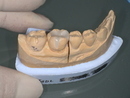

3. ジルコニアセラミッククラウンの作製

最新技術を用いて、 透明感と耐久性を両立した被せ物 を作製。

After

- 透明感のある自然なジルコニアセラミック

- 奥歯の口元が明るく、若々しい印象

- 健康的で自信のある笑顔を実現